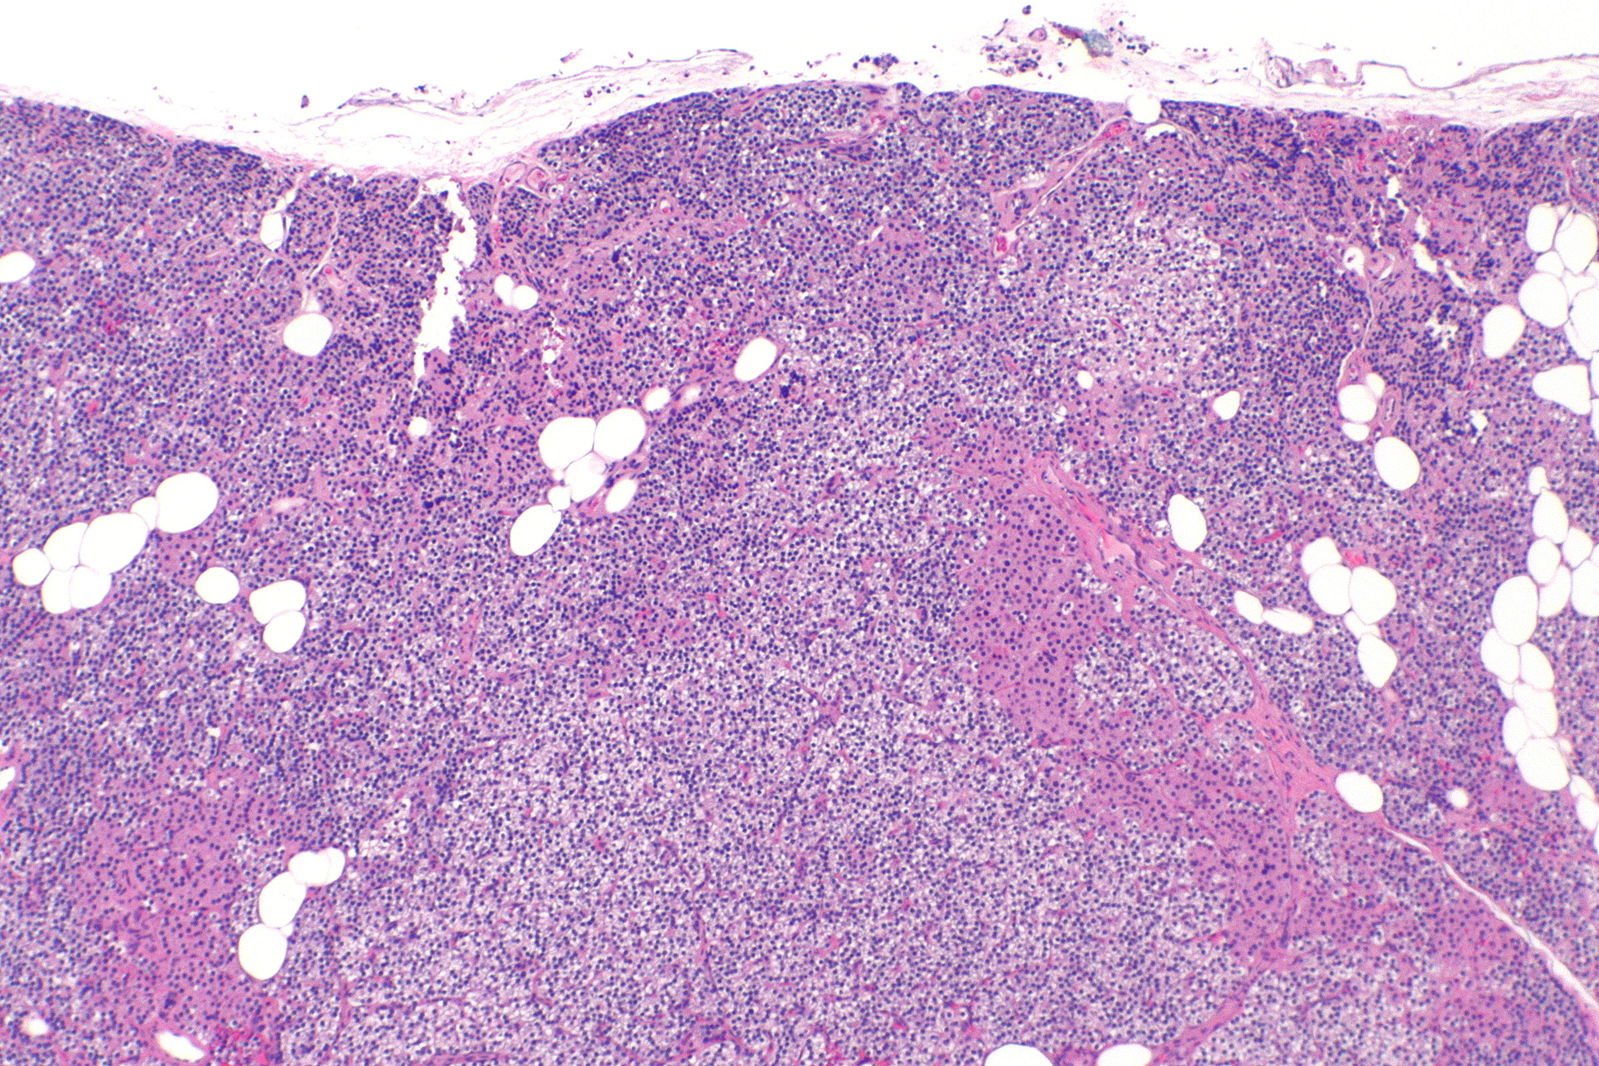

[7]Image credit: https://commons.wikimedia.org/wiki/File:Parathyroid_hyperplasia_--_low_mag.jpg